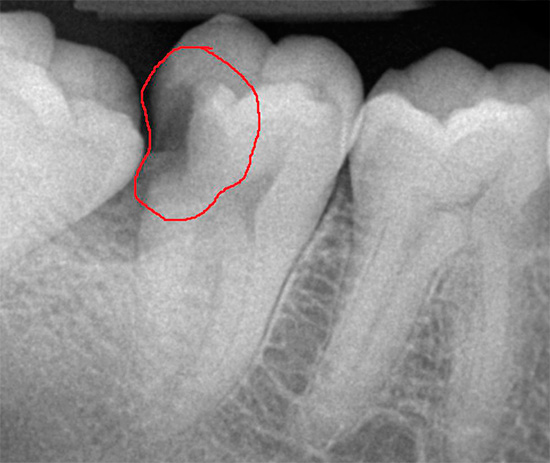

Un esempio di carie profonde in una radiografia è mostrato di seguito:

! importante

La carie profonda può svilupparsi anche senza lesioni visibili sulla superficie del dente. Sulla radiografia è chiaramente visibile e quindi spesso viene scattata una foto per diagnosticare e determinare l'estensione della lesione.